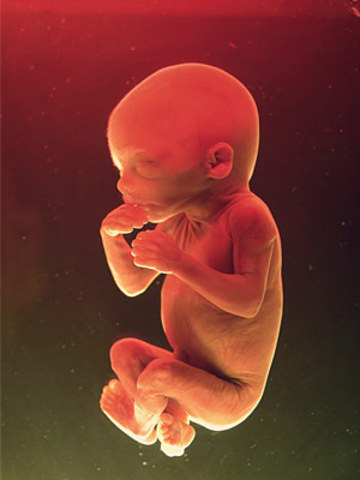

• 7 month

This fetus is now about 15 inches long and weighs between 1 and a half - 2 pounds. It can cry weakly and can suck its thumb. The fetus can make a variety of reflex movements: startle, grasp, and swim movements. The cerebral hemispheres cover almost the entire brain.